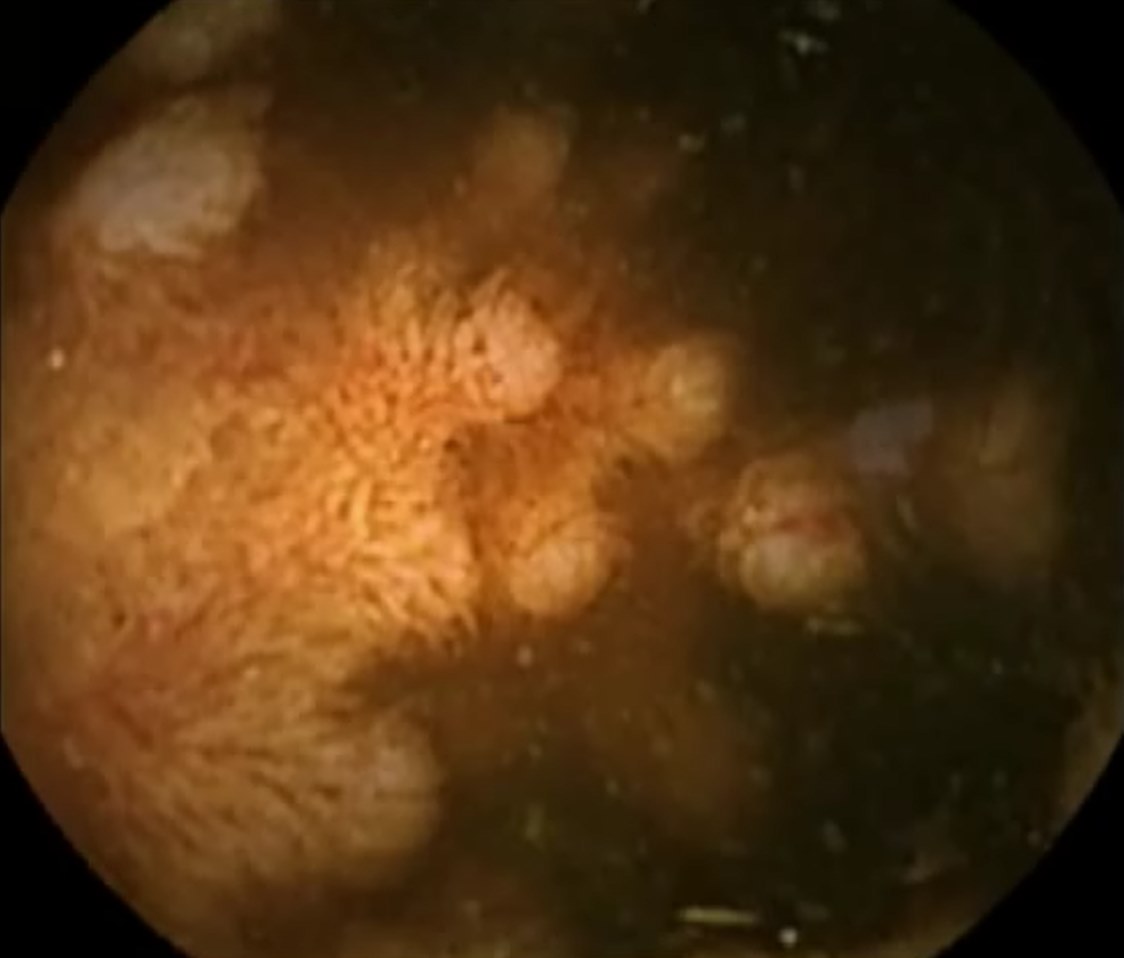

Capsule Endoscopy: Ileum Terminale, Lymphoid Hyperplasia